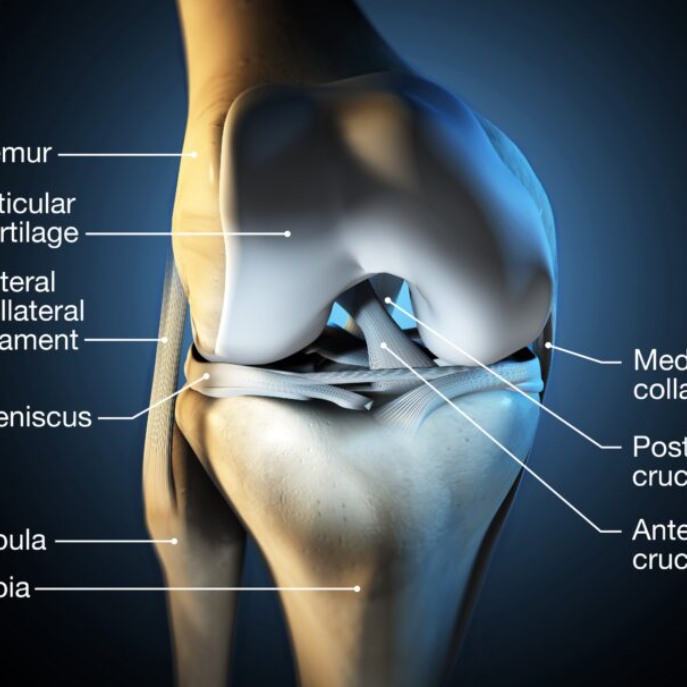

무릎 연골 손상의 주요 증상